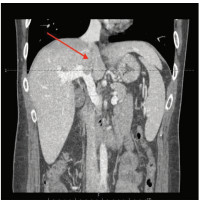

Multidisciplinary treatment of hepatocellular carcinoma with tumor thrombosis in the left portal vein: A case report

Jihong YANG, Guoxiang CHEN, Mo ZHOU, Jisen ZHAO, Yuan WANG, Yuanlong ZHOU

2021, 37(3): 666-679. DOI: 10.3969/j.issn.1001-5256.2021.03.031

Abstract(1185) HTML (567) PDF (3239KB)(69)

Abstract: